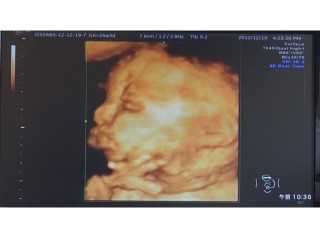

1ヶ月ぶりの検診♡ 長男の時にもやってもらった念願の4D! お顔がはっきり見えて完全に旦那似であることが分かりました(^^) 前回の検診で90%女の子と言われていましたが 女の子確定で大丈夫と言われ早速必要最低限のお洋服を買ってきました♪ スタイは現在手作り中です♡ 次の検診は2週間後! それまで待ち遠しいです(^^)